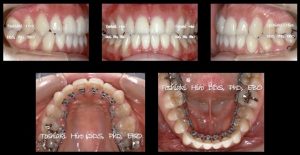

トップバッターは私、矯正歯科の意義と目的にはじまり、舌側矯正症例10数症例を紹介しました。